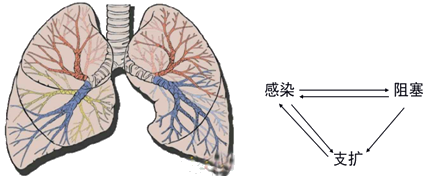

支气管扩张大多继发于急、慢性呼吸道感染和支气管阻塞。

『答案解析』支气管扩张大多继发于急、慢性呼吸道感染和支气管阻塞。